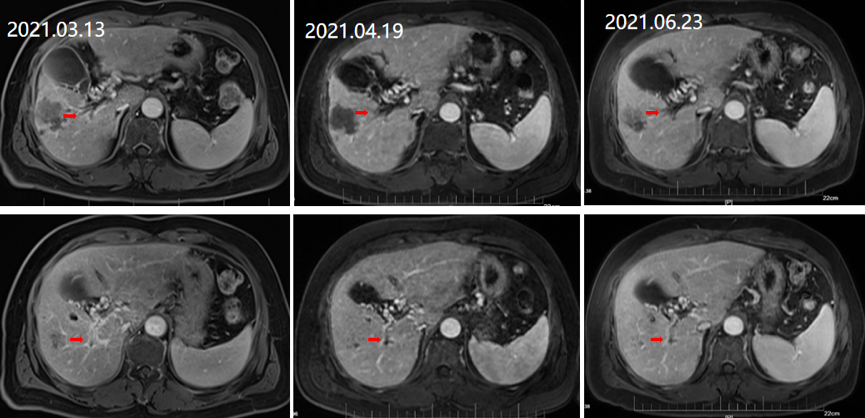

2021年3月13日、2021年4月19日、2021年6月23日复查MRI均提示维持治疗疗效稳定,总体评价仍为PR(图6)。

图片

图6.2021年3月13日、2021年4月19日、2021年6月23日复查MR